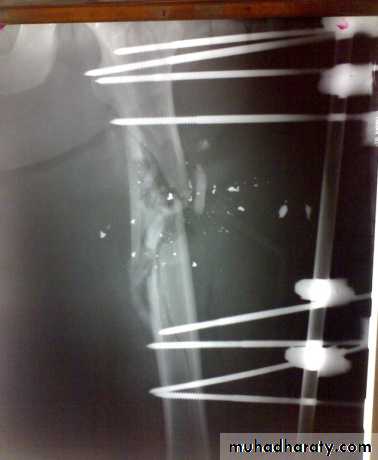

External fixation

Indications:Open injuries.

Multiple injuries to reduce operating time.

Bone transport for bone loss.

Displaced and/ or comminuted lateral or medial tibial condyle fracture

Treatment:ORIF.

Associated ligament injury repaired.

Bicondylar fracture: needs ORIF with plate and screws or external fixation.